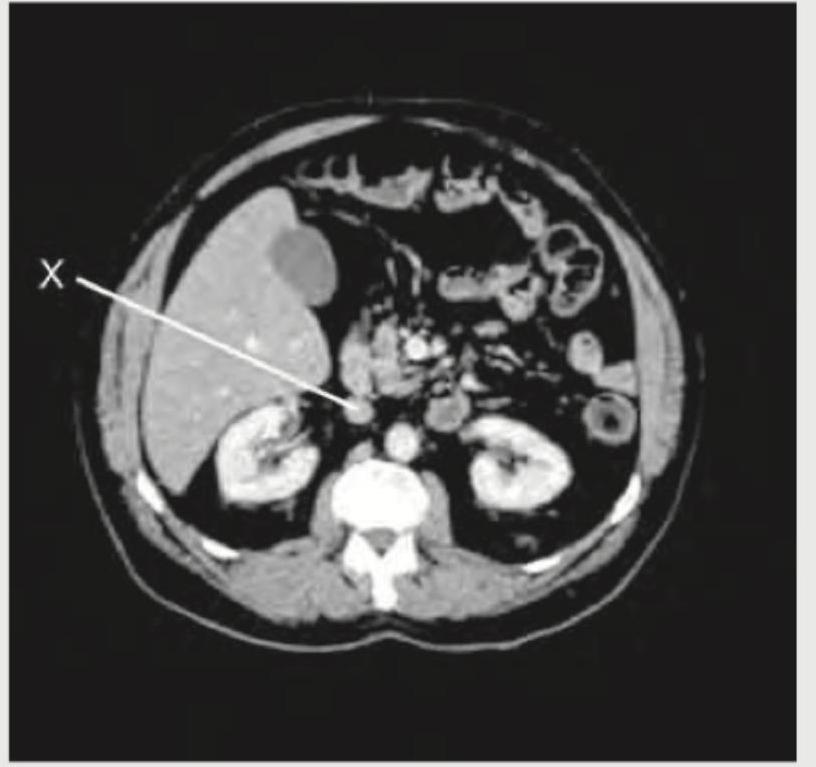

The following CT abdomen shows:

Explanation: ***Inferior vena cava*** - The structure labeled 'X' is a large, **thin-walled vessel** located to the **right of the vertebral body** and anterior to the right kidney, which is characteristic of the inferior vena cava. - The **inferior vena cava (IVC)** is typically more ovoid or flattened compared to the aorta, especially at this level, and drains into the right atrium. *Aorta* - The **aorta** is typically located to the **left of the vertebral body** and is generally more rounded and has thicker, more muscular walls than the IVC, appearing as a more uniformly circular structure. - The structure labeled 'X' is on the right side, making it unlikely to be the aorta. *Ureter* - Ureters are much **smaller in diameter** and are located more peripherally in the retroperitoneum, often seen near the psoas muscles. - The structure indicated by 'X' is a large, central vessel, not consistent with a ureter. *Superior mesenteric artery* - The **superior mesenteric artery (SMA)** originates from the aorta and is typically seen anterior to the aorta, often surrounded by fat and vessels of the superior mesenteric vein. - The structure 'X' is a major vein, not an artery, and is positioned more posteriorly and to the right of the midline compared to where the SMA would typically be found.